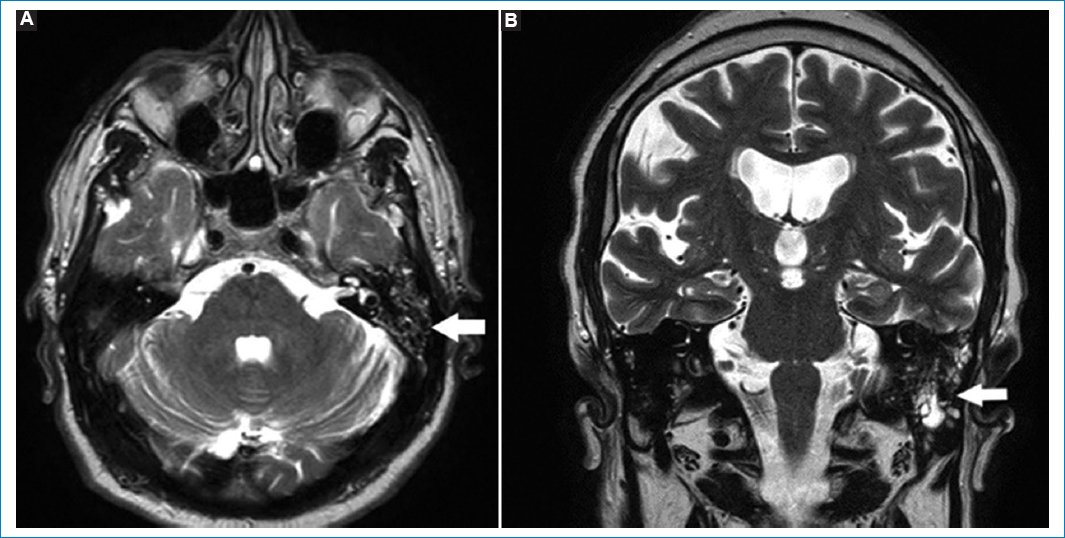

La presencia de adenopatías en cuello debe ser informada. Recordemos que las adenopatías mayores de 1 cm, en el eje corto, cambios en la señal en el tejido graso vecino, necrosis, calcificaciones o cambios en el hilio graso deben considerarse sospechosas de malignidad (Fig. 11)1,31.

Figura 11. Adenopatías en cuello. Secuencias ponderadas en T1. Cortes: axial (A) y coronales (B y C). Las flechas señalan distintos pacientes en los que fue informada la presencia de adenopatías, en contexto de un linfoma en una paciente de 27 años.

Es muy común el hallazgo de lipomas en el tejido celular subcutáneo. Se caracterizan por su naturaleza benigna y lento crecimiento. Dado su contenido adiposo son hiperintensos en T1 y T2 e hipointensos en STIR (Fig. 12)32.

Figura 12. Lipomas en cuello. Cortes axiales T1 (A) y T2 (B), y corte sagital T1 con gadolinio (C). Las flechas indican la presencia de imágenes redondeadas, bien delimitadas, hiperintensas en T1 y T2. Corresponden a lipomas en la región occipital.

La RM es el método de elección para valorar adenopatías en el espesor del tejido glandular parotídeo. La visualización de ganglios (menores de 1 cm), ante la ausencia de lesiones focales vecinas, puede considerarse como normal (Fig. 13)33.

Figura 13. Secuencias potenciadas en T2. Cortes coronales (A y B) y axial (C). Se visualizan formaciones redondeadas en el parénquima de las glándulas parótidas. Corresponden a adenopatías fuera del rango adenomegálico (flechas).